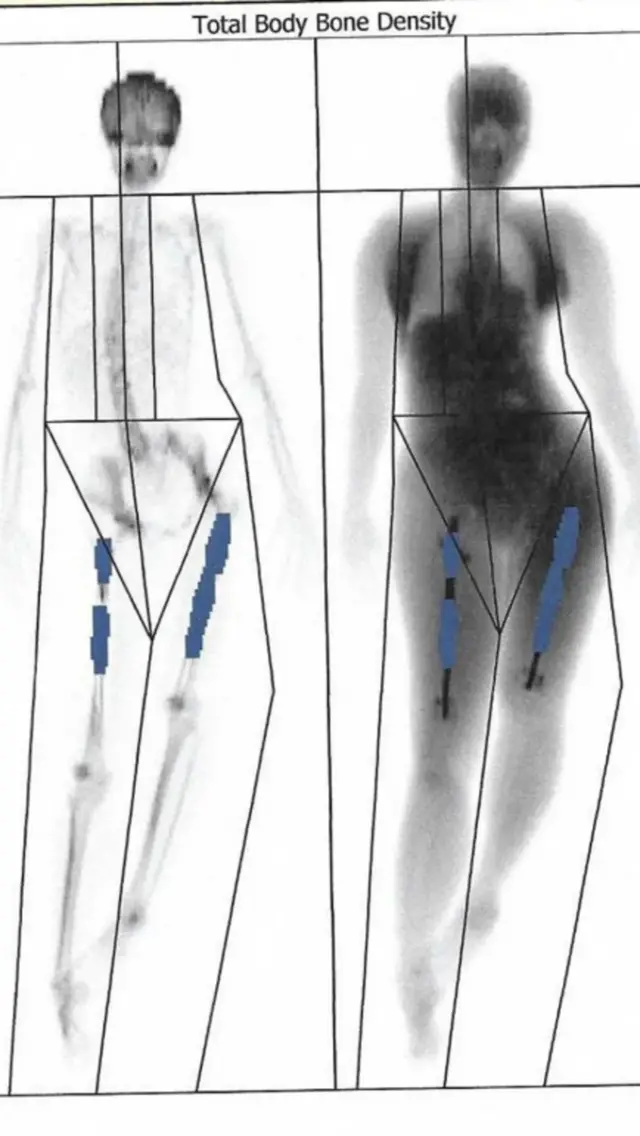

Ilejn je uradila snimak koji je potvrdio njene strahove.

Šipka-implant u njenoj levoj nozi je probila butnu kost, najjaču kost u ljudskom telu.

Šest nedelja kasnije, snimci njene desne noge pokazali su da ne raste kako treba kost koja treba da popuni prazninu između slomljenih krajeva kosti.

Njena butna kost je izgledala kao dve kosti spojene metalnom šipkom-implantom.